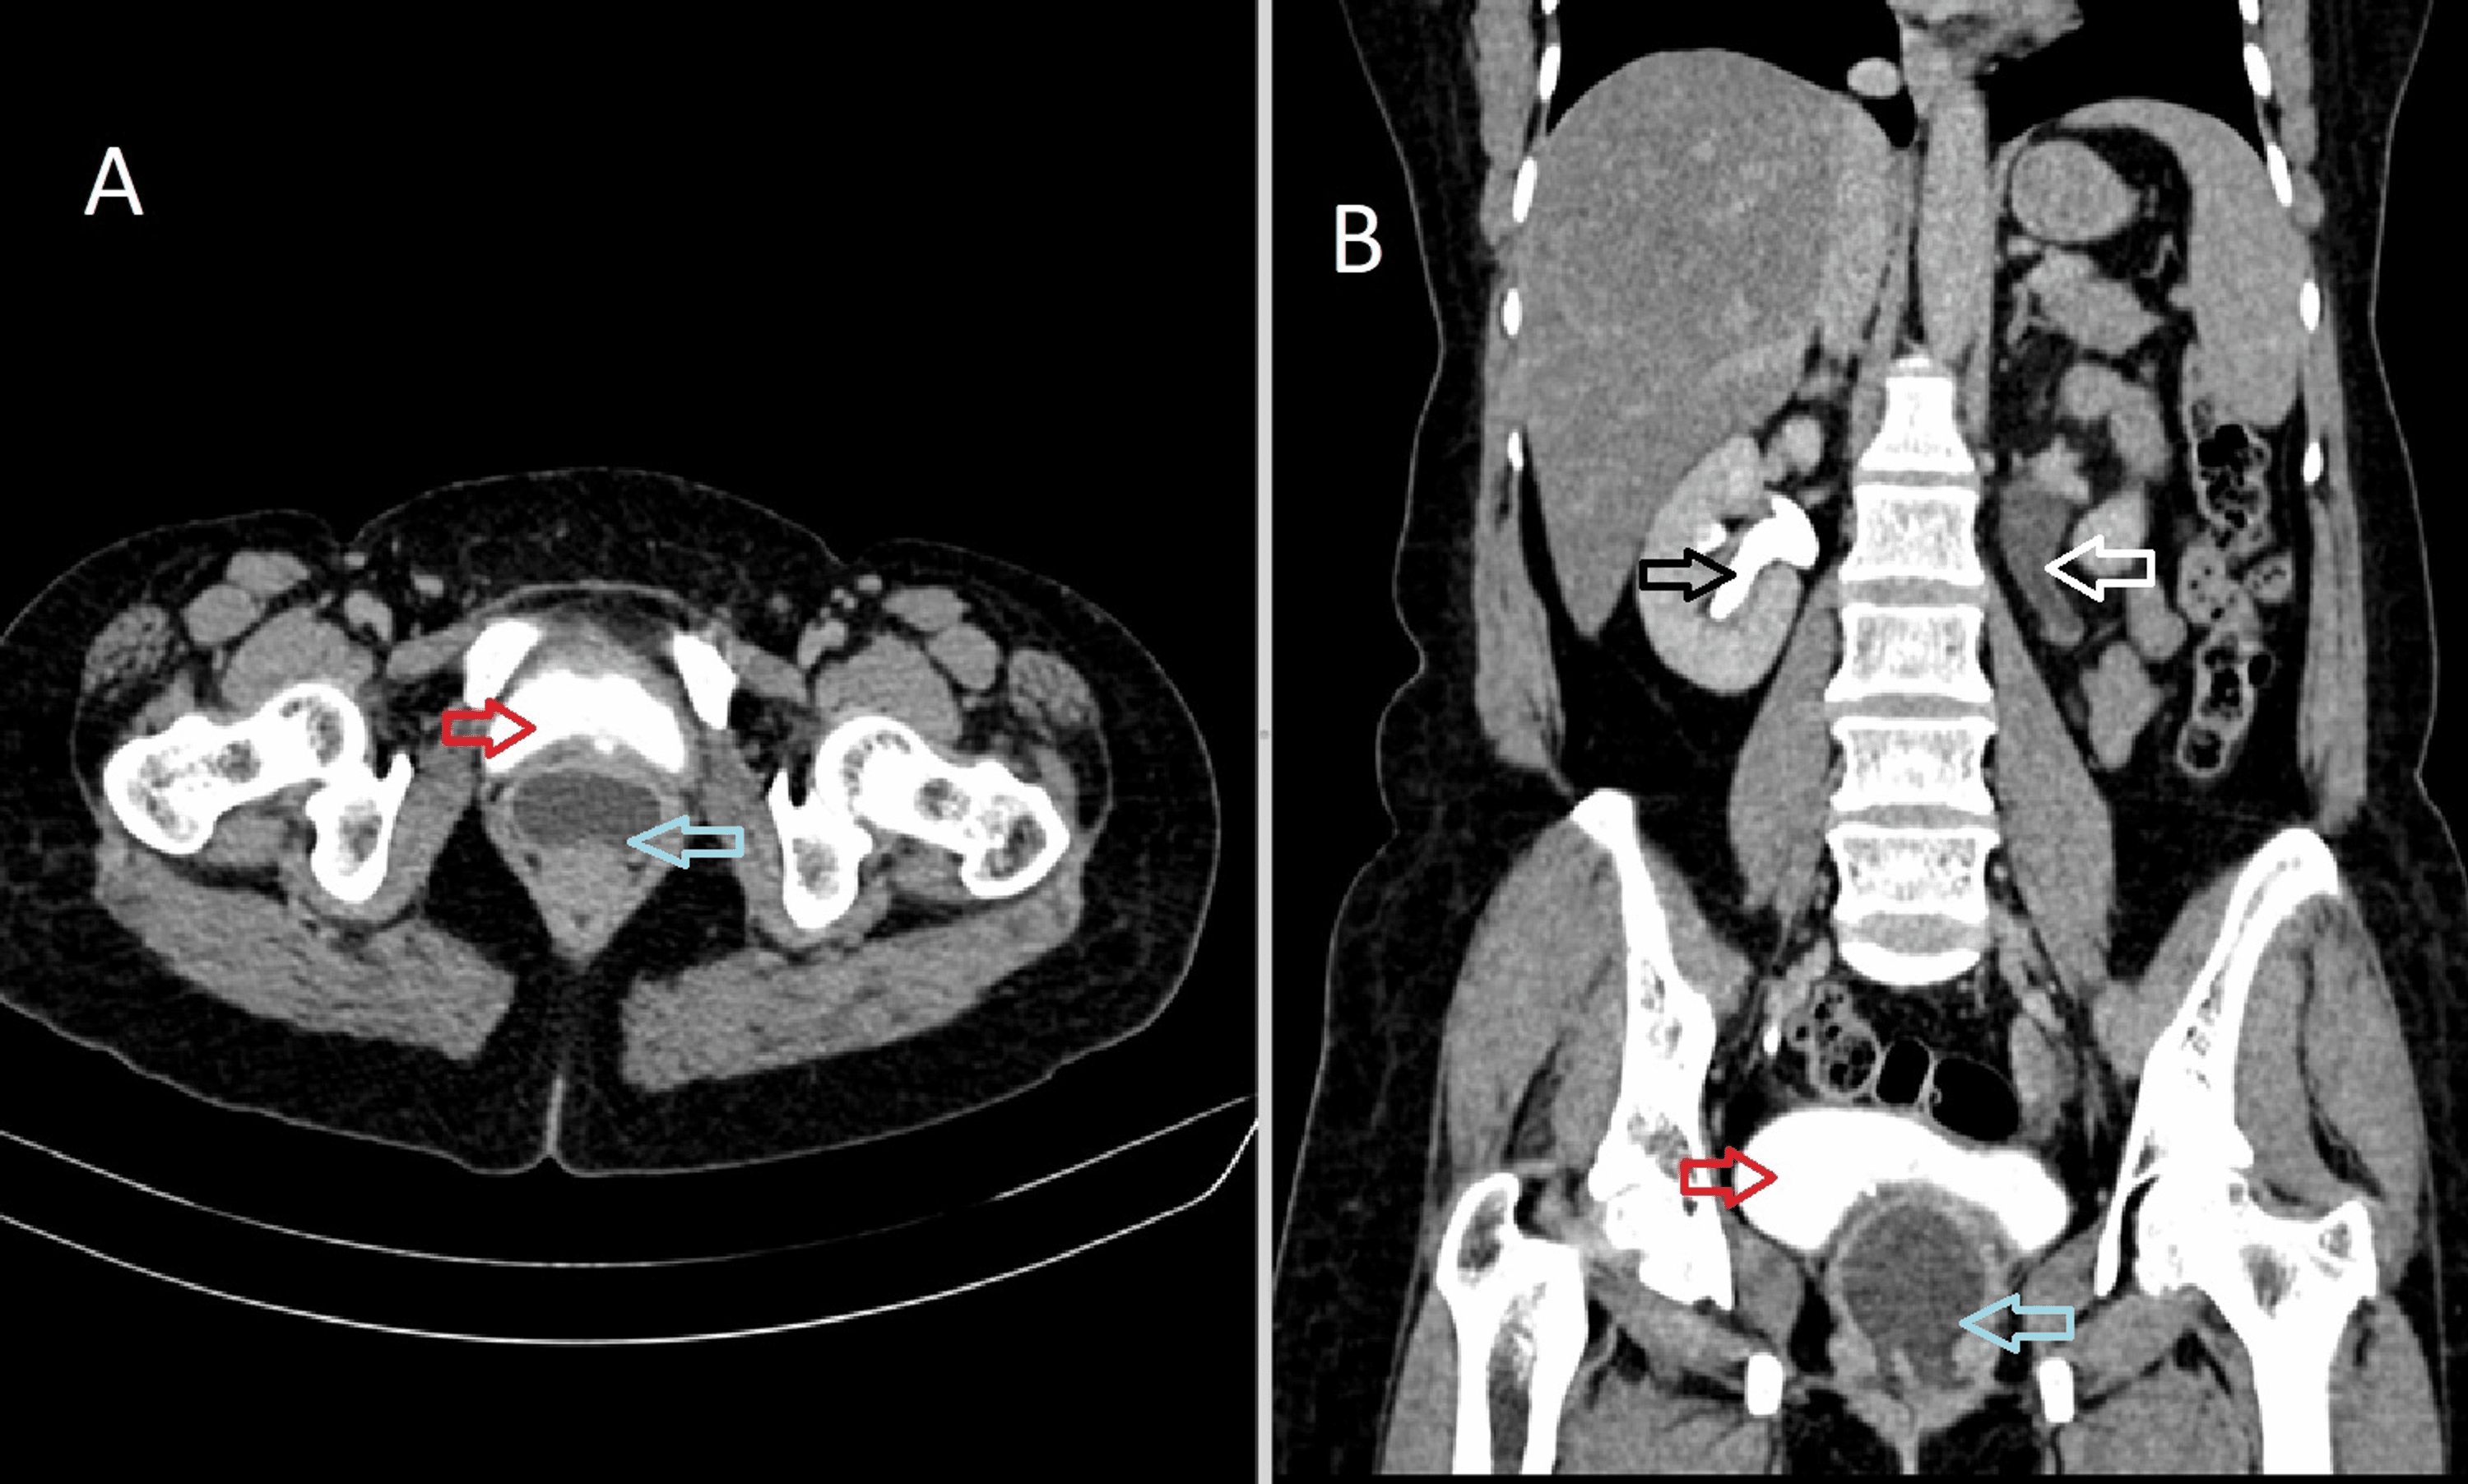

Figure 1 from A CASE OF RECTOVESICAL FISTULA AFTER LAPAROSCOPY ASSISTED Post Hysterectomy Fistula vesicovaginal and ureterovaginal fistulas are perhaps the most feared complications of female pelvic surgery. in contrast to obstetric and irradiation fistulas, the typical postsurgical (post hysterectomy) fistula is the result of more direct and. The technique consists of a circumferential ellipsoid incision around the vvf, with wide mobilisation of the vaginal epithelium in all directions. vesicovaginal and. Post Hysterectomy Fistula.